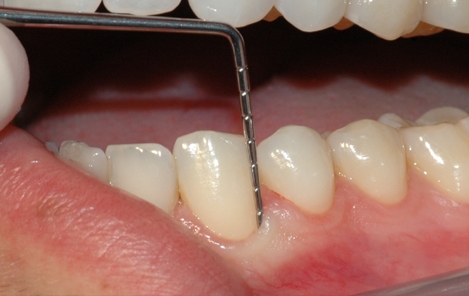

Tannstensfjerning, puss og poléring

Etter undersøkelsen er det vanlig at tannlegen eller tannpleieren fjerner tannstein og misfarging fra tennene. Tannstein består for det meste av kalkstoffer fra spyttet som avleires og legger seg på tannflaten som et hardt belegg. Det sitter så godt fast at det er nærmest umulig å fjerne på egen hånd med tannbørsten.

Tannlegen eller tannpleieren kan fjerne både tannstein og overfladiske misfarginger ved å rense, pusse og polere tennene. Tannsteinen fjernes enten med maskin eller ved å skrape den bort med håndinstrumenter. Misfarginger kan poleres bort med en spesiell pussepasta som inneholder ekstra slipemiddel. Alternativt går det an å benytte saltblåsing for å fjerne misfargingene.